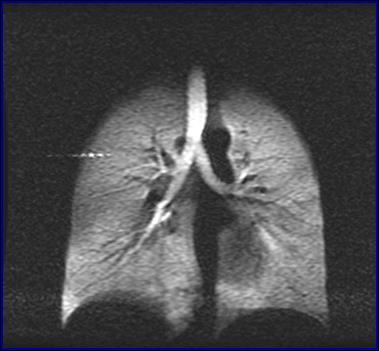

无码影片 武汉物理与数学研究所研究员周欣、中科院院士叶朝辉带领的科研团队克服技术难关,研制出具有自主知识产权的人体肺部气体磁共振成像系统。该系统弥补了传统磁共振成像不能检测肺部空腔结构的缺陷,成功“点亮”人体肺部,且能同时获得肺部气气、气血交换的功能信息,成为肺癌等重大疾病早期科学研究和诊断的新利器。目前,该成果已转移转化成立产业化公司,且正在申请医疗器械注册证。2018年7月在同济医院建立了第一个肺部气体磁共振临床检测中心,用于大规模临床病例获取工作。

左:核心装置超极化气体发生器 右:我国首幅人体肺部气体磁共振成像图